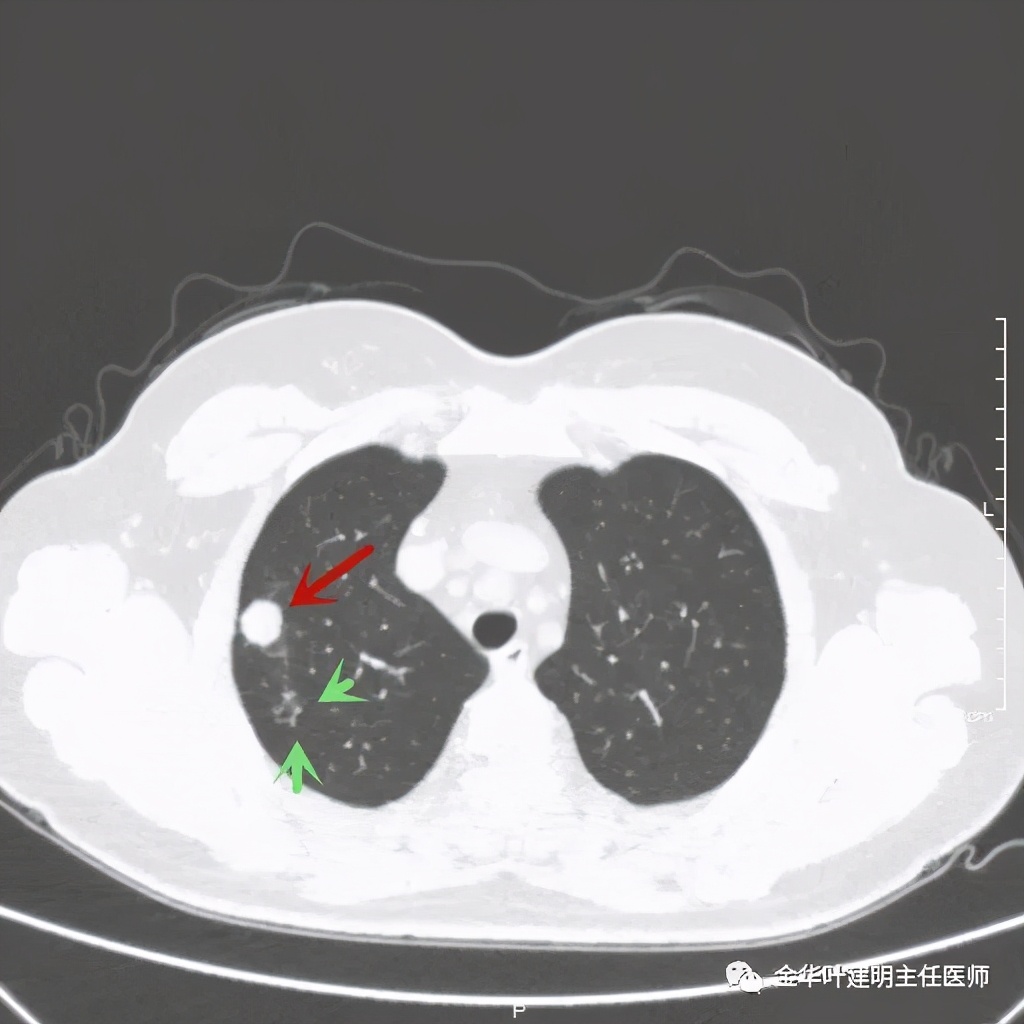

紫色箭头示病灶与胸膜很近,但无牵拉凹陷,绿色箭头示附近有微小其他病灶

主病灶非常光滑

上图同样示与胸膜近,但无牵拉

上图示病灶内侧有个小的空泡